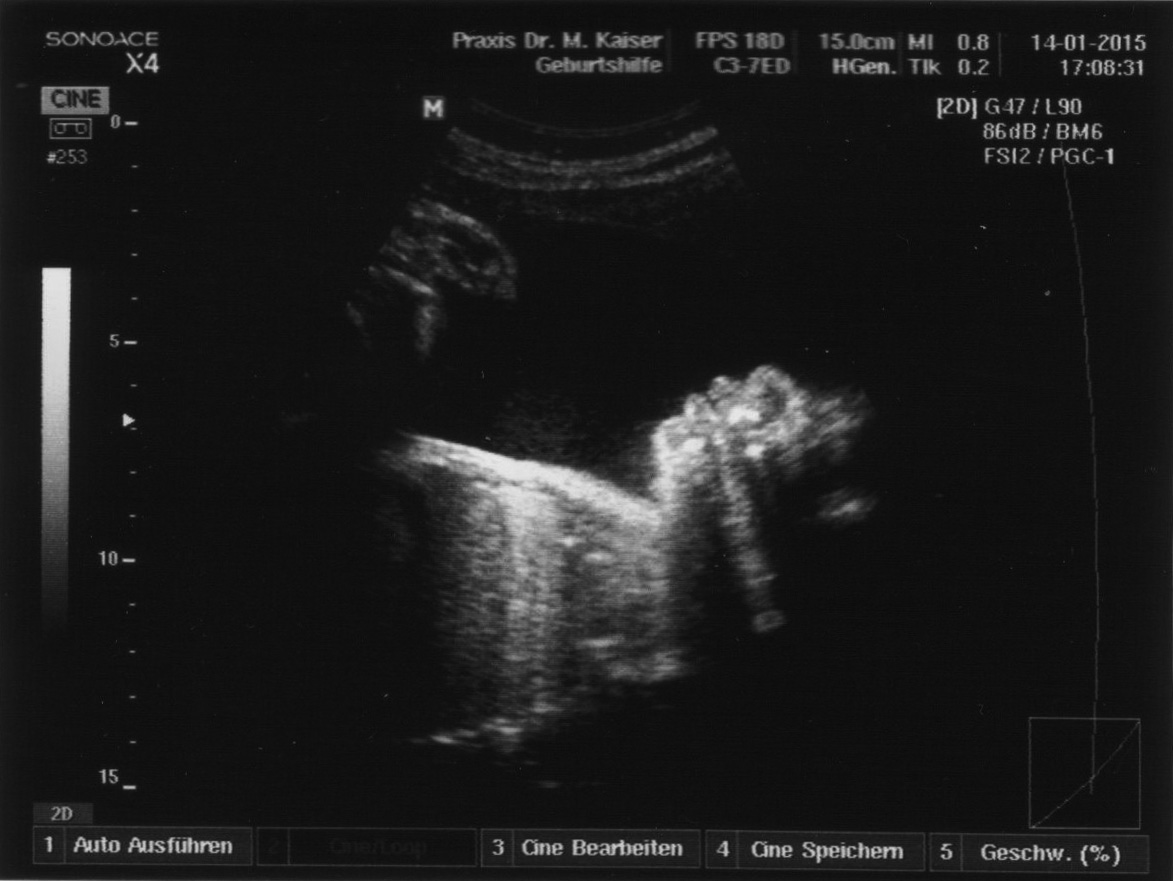

Auf dem neuesten Ultraschallbild kann man Lippen und Nase erkennen. Jetzt stellen wir uns natürlich die Frage, wessen Nase bekommt sie denn?

auf dem Ultraschallbild erkennt man oben rechts das Gesicht